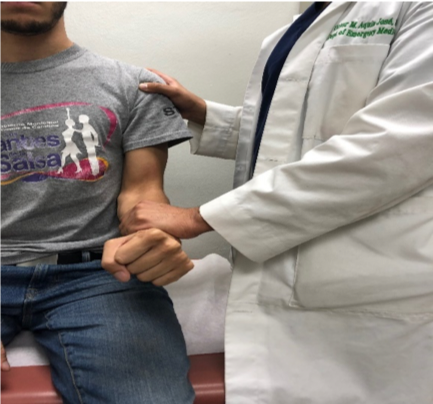

Bicipital tendinitis is a condition caused by inflammation of the long head of the biceps muscle’s tendon. It’s commonly caused by sudden overuse of the muscle and rotator cuff pathology such as muscle or tendon tears, chronic impingement, multidirectional shoulder instability, calcifications, and deconditioning. Signs in physical examination correlating with bicipital tendinitis are pain at the bicipital groove and a positive provocative test such as Speed’s test and Yergason’s test, although studies have shown that their sensitivity might be poor.1